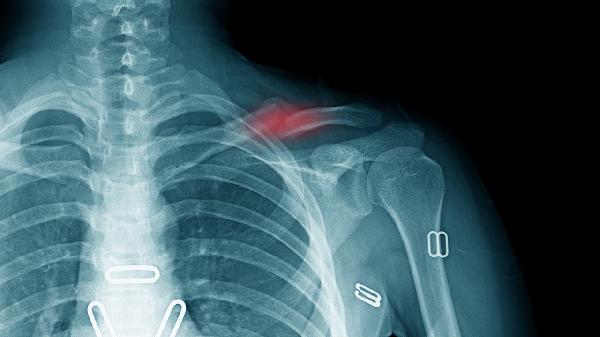

每3-6个月进行胸围测量和肺功能检查,儿童患者需监测骨龄发育情况。拍摄系列胸片对比肋弓角度变化,重度进展者需评估是否合并脊柱侧弯。生长发育期患者建议每季度评估营养状况。